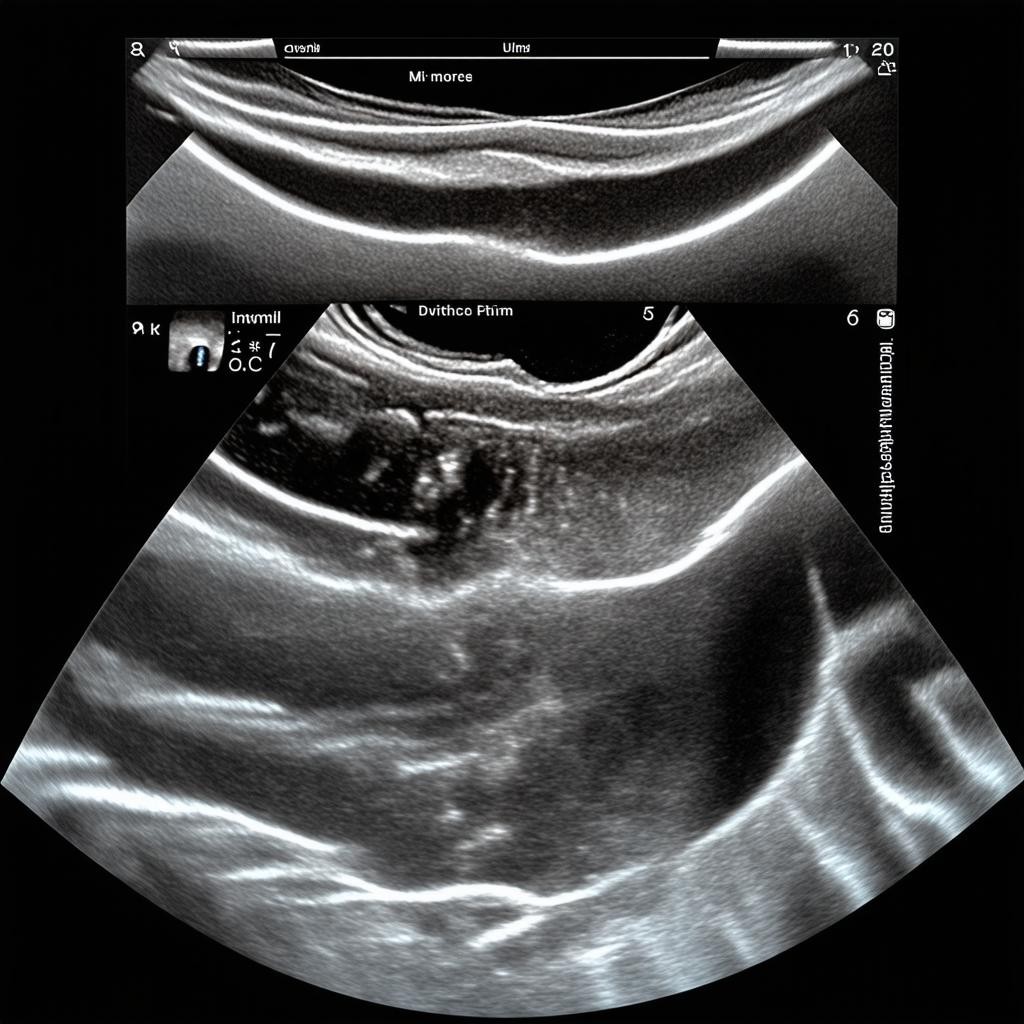

Ультразвуковое исследование (УЗИ) представляет собой один из наиболее безопасных, информативных и доступных методов диагностики в современной медицине. Этот неинвазивный способ обследования основан на использовании высокочастотных звуковых волн, которые человеческое ухо не воспринимает. Ультразвуковые волны проникают через ткани организма и, отражаясь от них, создают изображение внутренних органов на экране монитора. Благодаря отсутствию ионизирующего излучения УЗИ можно проводить многократно без риска для здоровья пациента, что делает его незаменимым инструментом для динамического наблюдения за течением заболеваний.

Основой ультразвукового исследования является пьезоэлектрический эффект, который преобразует электрическую энергию в механические колебания - ультразвуковые волны. Специальный датчик, называемый трансдьюсером, генерирует ультразвуковые волны частотой от 2 до 15 МГц. Эти волны проходят через ткани организма с разной скоростью, зависящей от плотности и упругих свойств тканей. При переходе из одной среды в другую часть волн отражается и возвращается к датчику, который улавливает эти отраженные сигналы. Компьютерная система обрабатывает полученную информацию и создает двухмерное или трехмерное изображение в реальном времени.